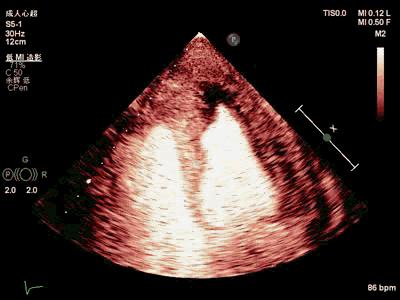

超声心动图(外院B,2019-3-31):左室舒张功能减低(图4)。

图4. 外院B超声心动图。

典型的超声心动图表现为心内膜增厚,多位于心室流入部及心尖部,致心尖部心腔变窄甚至闭塞。急性期心内膜与心肌间界限不清,随着病情进展,受累部位可出现附壁血栓,同时伴有舒张功能障碍的血流动力学特点。本例患者外院就诊时尚未形成血栓,超声表现无特异性,故诊断难度较大,转诊至我院时,符合典型Loeffler心内膜炎表现。当超声心动检查时发现心内膜普遍增厚伴血栓形成,心尖部心腔闭塞,高度警惕Loeffler心内膜炎。